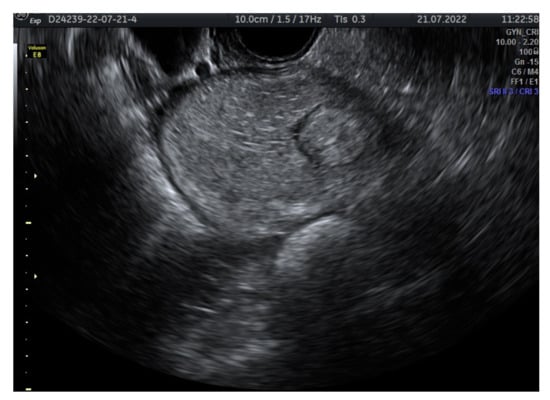

2.2. Mature Cystic Teratoma

2.2.1. Ultrasound Appearance